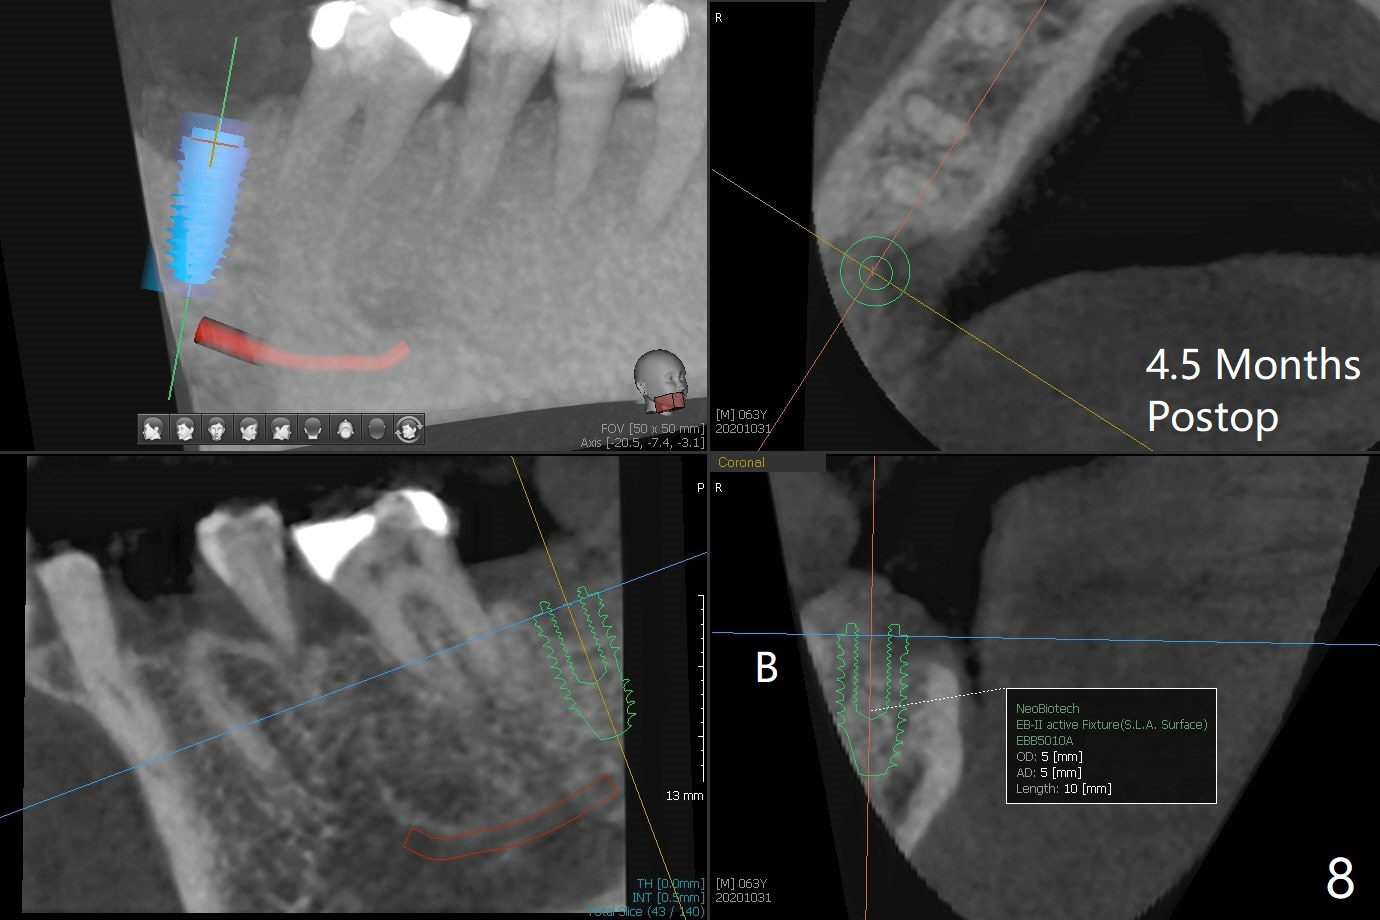

After removing the fractured apices of the tooth #31 (Fig.1,2), it is extremely difficult to start osteotomy with 7.3 mm stopper free hand. Since sticky bone (Fig.3,4) and PRF membrane are available, socket preservation is performed with bone condenser and PGA (Fig.5). If a surgical guide were fabricated, immediate implant would finish quicker. The socket opening is almost closed without pain or swelling 8 days postop (Fig.6). Clinically, the ridge is apparently wide with enough keratinized gingiva 4.5 months postop. The original ridge height seems to restore as the sticky bone undergoes condensation vertically (Fig.7, as compared to Fig.5). With bone graft, a 1.5 mm longer implant could be placed (Fig.8). The gingival pocket (Fig.9 white dashed line) seems to be an excellent cultivation bed for bone graft, although the latter also undergoes buccolingual shrinkage coronally (Fig.10).